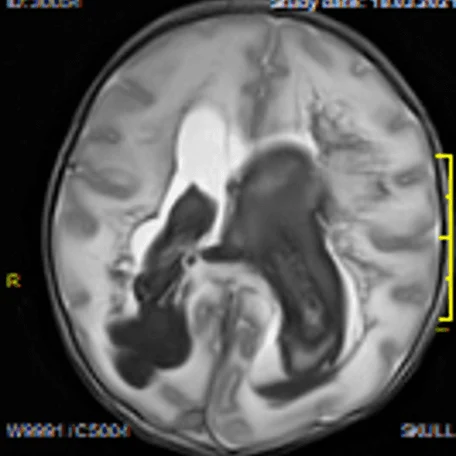

Внутрижелудочковые кровоизлияния

Чаще возникают у недоношенных новорожденных. Основным источников ВЖК служат сосуды эпендимы мозга и сосудистые сплетения. Способствующие факторы: затяжные или быстрые роды, перинатальная гипоксия, коагулопатии, нестабильность гемодинамики у новорожденного.